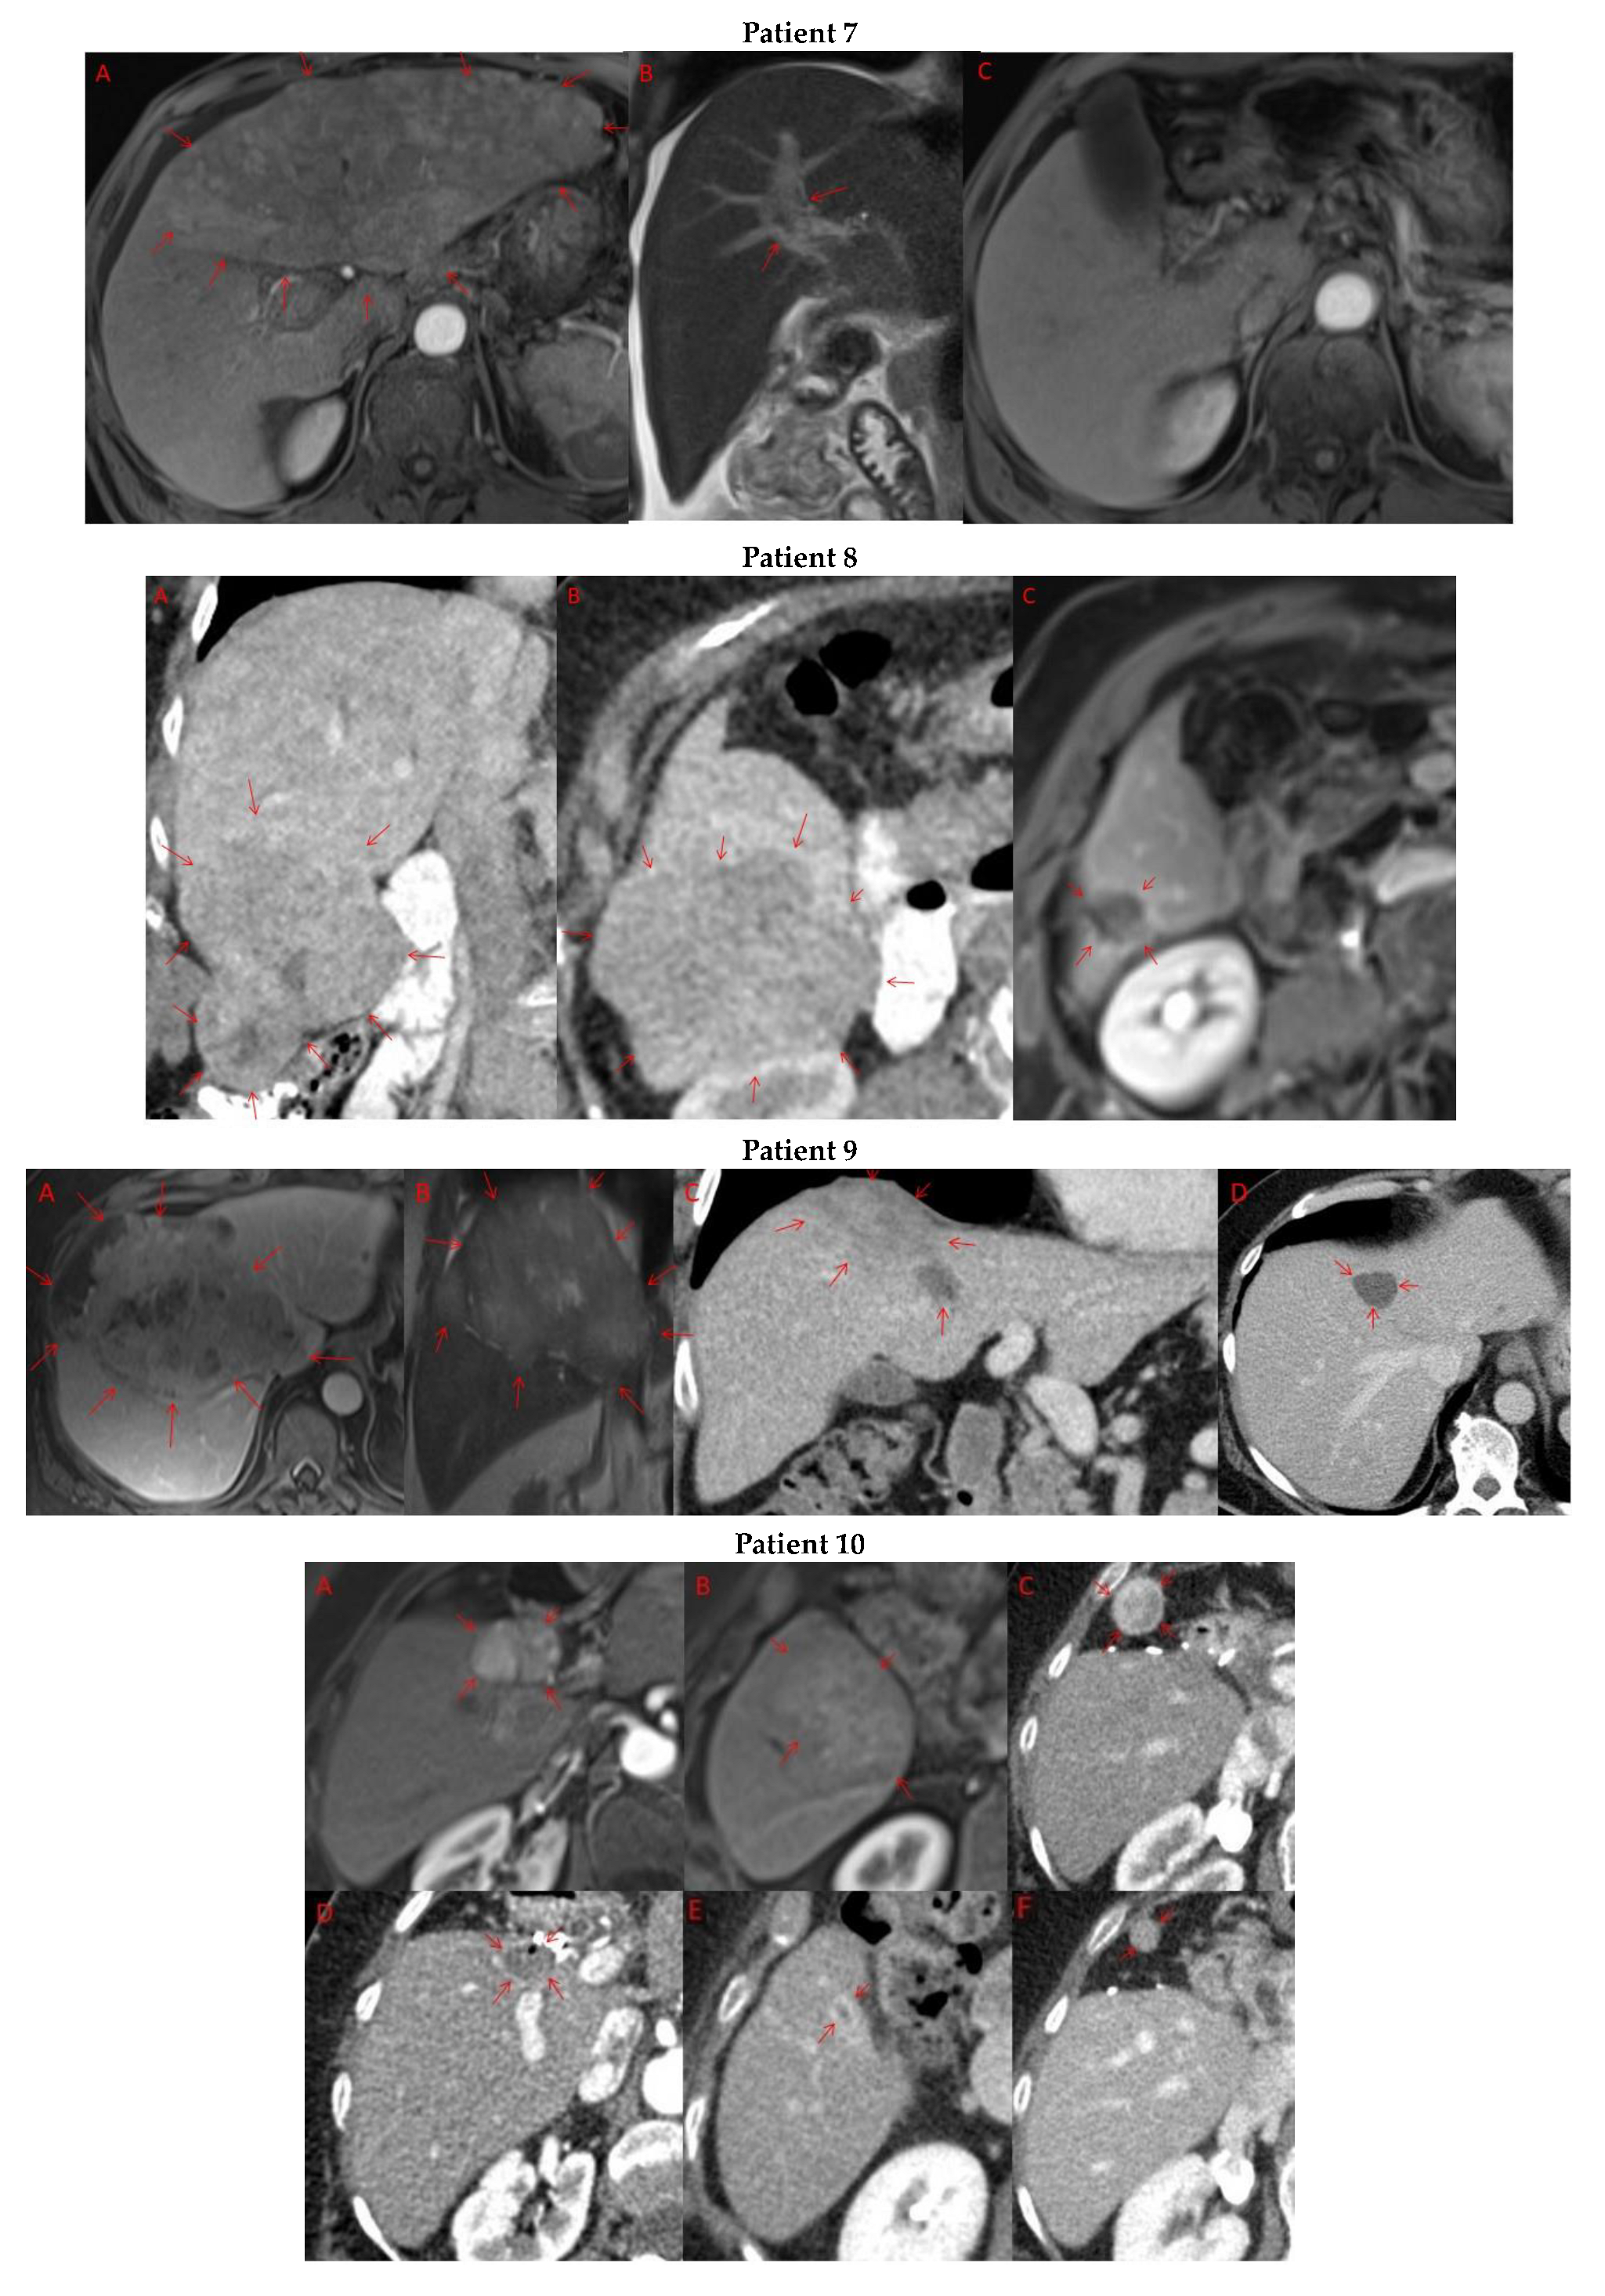

Pre- and post-treatment imaging for all exceptional responders is provided (Figure 3).

Figure 3.

Imaging findings in patients (n = 11) with complete response to neoadjuvant immunotherapy. Cross-sectional imaging for each patient with complete response to immunotherapy. Images represent the scan most recently taken prior to beginning the course of neoadjuvant treatment and the scan taken most recently after completion. (Patient 1) MRI showing large pre-treatment infiltrative tumor (A) followed by decrease in size from 10 cm to 5.6 cm status post 15 cycles of immunotherapy (B). (Patient 2) Large ill-defined 11cm tumor at diagnosis (A) followed by decrease in size to 3.6cm after 1 cycle Atezolizumab (B). (Patient 3) 13.3 cm mass with periportal lymphadenopathy (A) and subsequent decrease in size to 6.9 cm after 5 cycles of immunotherapy+1 round Y90 (B). (Patient 4) 8.1 cm mass in segment VIII with extension to right hepatic vein (A,B), and post-treatment tumor shrinkage after 11 cycles immunotherapy and locoregional treatment (C). (Patient 5) Recurrent scattered HCC lesions after previous resection (A–C). Near complete resolution after 4 cycles of immunotherapy and 1 Y90 (D,E). (Patient 6) 8 cm mass in segment II/III with portal vein invasion (A,B) and complete resolution after 22 cycles immunotherapy, Y90 and SBRT (C). (Patient 7) Infiltrative 20.3 cm mass in the left lobe with extensive tumor-in-vein in portal venous system (A,B) followed by complete resolution on 20 cycles immunotherapy, locoregional treatment and SBRT (C). (Patient 8). 7.1 cm mass in the right lobe (A,B) with reduction to 1.7 cm after 31 cycles immunotherapy (C). (Patient 9) 14.7 cm mass in the right hepatic lobe (A,B) shrinking to 5.8 cm after treatment (C,D). (Patient 10) Patient post-partial resection of segment IV/V for HCC with recurrence demonstrating 3.2 cm segment V/VIII lesion (A), a 4 cm lesion in the Right lower lobe (B) and a peritoneal metastasis (C). After treatment with 9 cycles immunotherapy + multiply Y90 treatments tumor size shrunk significantly (D–F). (Patient 11) Patient post-right hepatectomy for HCC with multiple diffuse recurrent nodules in the liver with largest measuring 2.6 cm (A,B). Post treatment imaging showing no evidence of disease (C).